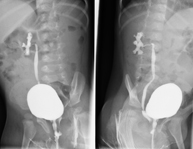

- Cistografía (CUMS)

La cistouretrografía miccional seriada consiste en la obtención de imágenes radiológicas para valorar la anatomía y la función de la uretra y la vejiga con la administración de contraste yodado a través de una sonda vesical.